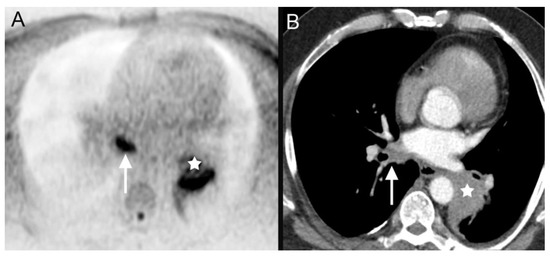

| 4 | bronchial carcinoma (Figure 4) | ||

| 4 | bronchial carcinoma | systemic chemotherapy |